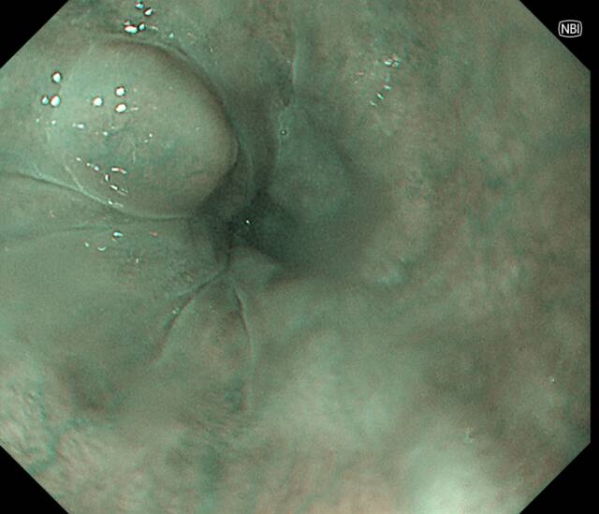

在奥林巴斯X1设备及高清放大内镜的支持下,新镜界全面采用“精准取活检”技术。

在检查过程中,若发现高度怀疑早癌或诊断不明确的病灶,及时与患者家属沟通,经同意后,进行精准靶向活检。避免对典型良性病变或计划行诊断性ESD/EMR的浅表癌进行活检。

运用奥林巴斯X1设备及高清放大内镜,针对可疑区域精准取样,检出率大幅提升。